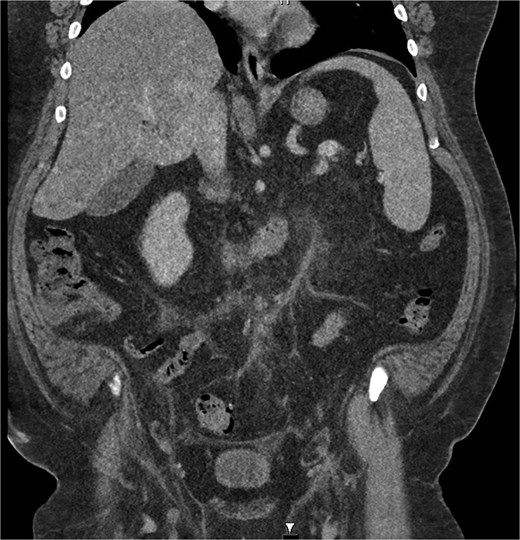

He received intravenous cannulation and initial fluid resuscitation. His blood demonstrated leucocytosis (11.59), C-reactive protein of 213, and a normal coagulation profile. The lactate measured 1.3. CT imaging with portal venous contrast demonstrated sigmoid diverticulitis, complicated by inferior mesenteric vein thrombosis. Features of mesenteric fat stranding were seen surrounding the IMV and left colic branch, with reduced opacification of the vessels in this area (Figs 1 and 2). There was no discrete collection identified. The patient returned a positive blood culture, with growth of Bacteroides fragilis present from the day of admission.

Coronal CT image demonstrating portal venous contrast phase abdomen, with inflammatory fat stranding and wall enhancement of the IMV.